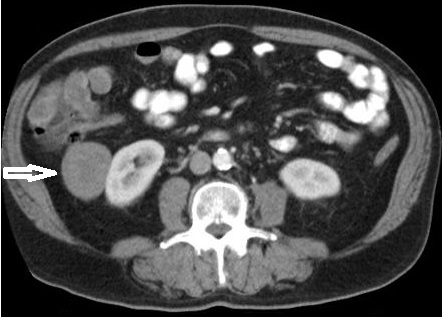

Fase nefrográfica o portal

Se logra a partir de los 80 a 180 segundos posteriores a la inyección del contraste; el medio de contraste se encuentra en los túbulos colectores y asa de Henle durante esta fase y su utilidad se basa en el aumento homogéneo del parénquima renal, lo que permite una mejor delimitación de la masa renal.

Durante esta fase se presenta el mayor realce de los tumores sólidos, por lo que se logra una mejor caracterización de las masas indeterminadas. En un estudio sobre la caracterización de las masas renales menores a 3 cm se concluyó que durante las exploraciones en fase nefrográfica se permitió una mayor detección de lesiones y una mejor caracterización de las masas renales pequeñas que en las exploraciones de fase corticomedular 3-5 (Fig. 3).